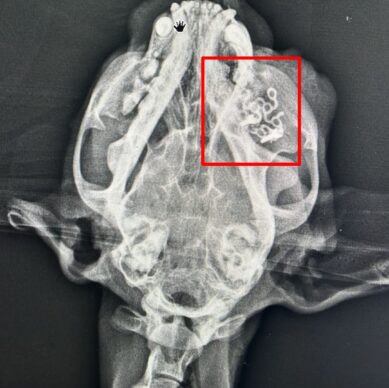

kafatası kemiği kırığı